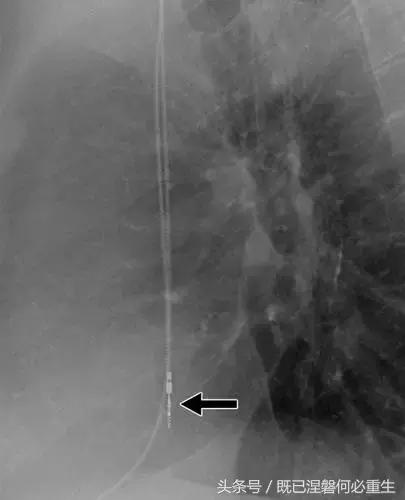

图。 9发生器引线断开。 移出的装置的放射线照片显示从末端完全退出的电极的外观(箭头)。 少数发电机没有容易识别的标志; 因此,制造商不能确定。